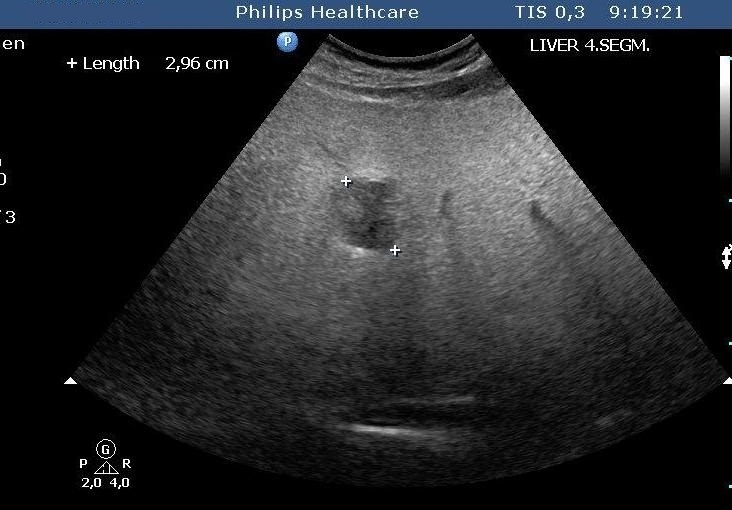

Figure 24: Metastases of a GIST tumour, US

The liver metastases of colorectal origin are usually characterised by a bit inhomogeneous hyperechoic structure sorrounded by a hypoechoic rim. (Figure 25)

Figure 25: Liver metastasis of rectal cancer, US

In the central area of bigger (4-6 cm in diameter) metastases necrosis can also develop as so called „target” form (or commonly called as bull’s eye sign).